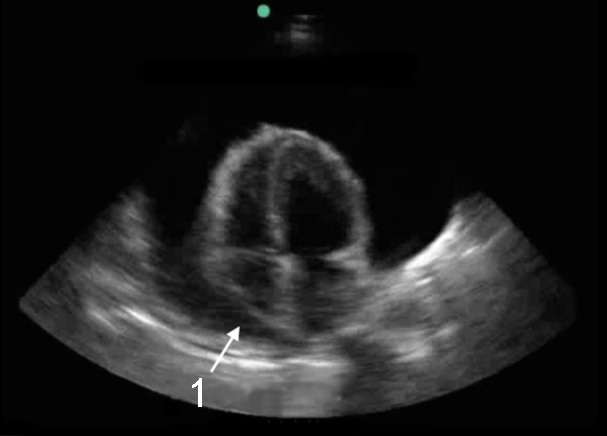

Imagen cardíaca de Taponamiento desde el plano apical de las 4 cámaras

1. Colapso diastólico de la aurícula derecha